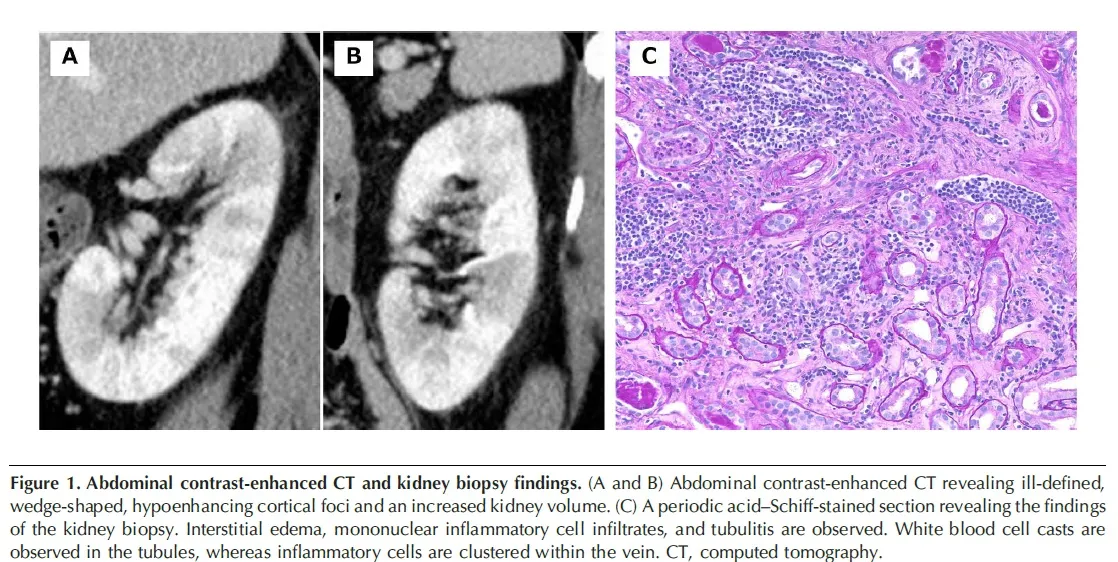

Uma tomografia computadorizada (TC) contrastada revelou focos corticais hipoatenuantes mal definidos e um aumento do volume renal (imagem abaixo).

Devido os níveis persistentemente elevados de Cr, mesmo após 3 meses da descontinuação do inibidor de checkpoint, o paciente foi internado para realização de biópsia renal. A avaliação urinária não identificou proteinúria, hematúria e piúria estéril, mas a microglobulina urinária β-2 aumentou para 3667 mg/L. A biópsia renal revelou nefrite tubulointersticial aguda. O tratamento com prednisolona foi iniciado para IRA relacionada ao inibidor de checkpoint, e os níveis de Cr diminuíram progressivamente para 1,53 mg/dl em seis meses.

2. A TC com contraste pode revelar áreas de baixa densidade nos rins